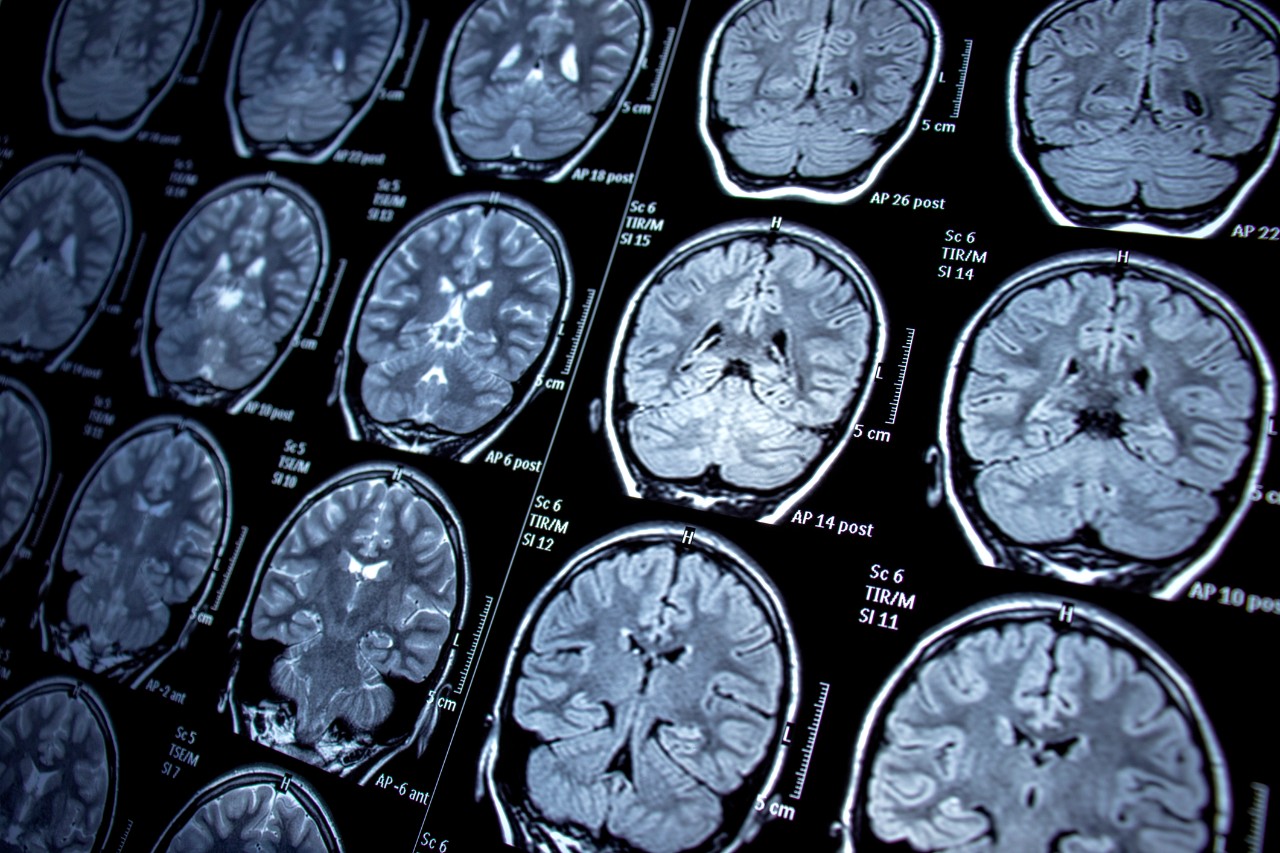

Researchers at the University of Cincinnati and Dell Medical School at the University of Texas at Austin (Dell Med) are leading a study using state-of-the-art neuroimaging techniques and artificial intelligence to identify changes in the brains among children of adults living with bipolar disorder — a debilitating condition that interferes with daily life due to its dramatic mood, energy and activity level shifts.

The study is the first of its kind to focus specifically on the progression of the disease over time via neuroimaging in children of parents with bipolar disorder.

The research leverages AI algorithms to discern variations in participants’ brains, combining imaging data with cognitive, clinical, early life adversity and psychosocial function measures. The result is a precise delineation of brain maturation for each person at risk of developing bipolar disorder.

The five-year longitudinal study uses functional magnetic resonance imaging to identify early signs that the brain is developing bipolar disorder. Participants ages 14-21 — a critical time when mania symptoms often develop — undergo annual brain scans to track changes in the brain. If they become depressed, suicidal or experience mania, the participants undergo additional brain scans to help researchers understand how the damage is unfolding.

Featured photo at top of brain scans. Photo/Nur Ceren Demir/iStock.